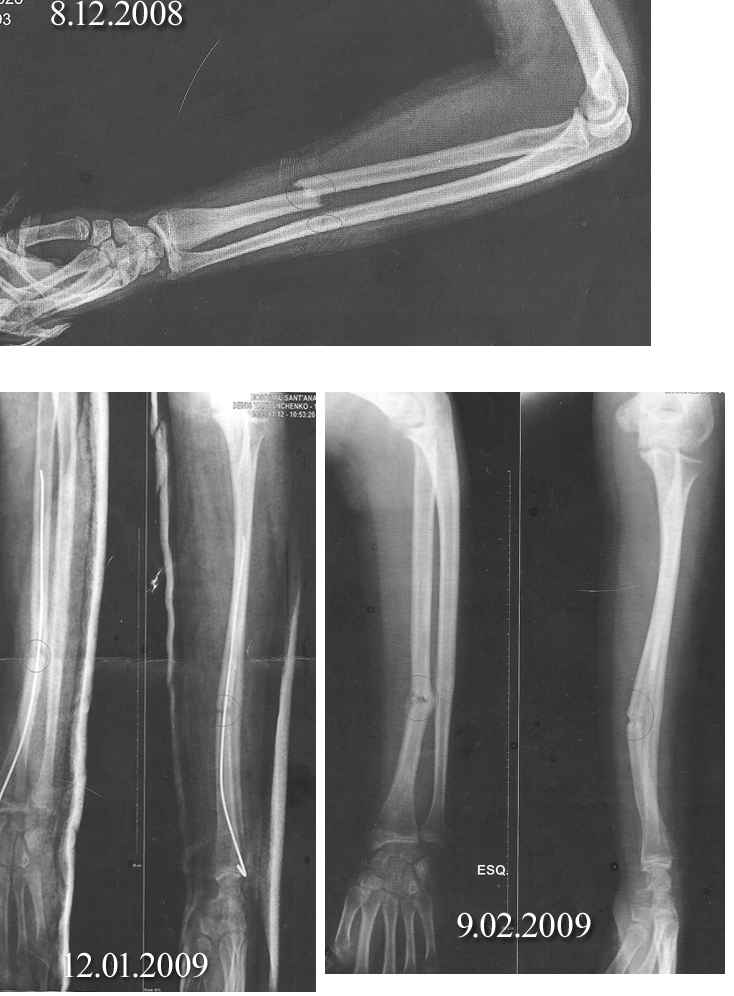

8.12.09 племянник (15 лет) поломал руку, поскользнулся и упал на брущатной дороге. Ему наложила гипс и вставили спицу...потом, 9.02. сняли гипс и выняли спицу. При этом племянник сказал, что боль была сильнее чем когда складывали руку...Обратите внимание на последний снимок, кость как бы согнулась углом, а со спицей была ровной. Может тот практикант, что вынимал спицу что то нарушил?...В результате, мальчик жалуется на то, что рука как не его и боится ею что либо делать...Одни врачи говорят, что может выровняться кость, другие - говорят, что обязательно нужна открытая репозиция с фиксацией металлической пластиной...Что делать? Как поступить? Делать ли операцию?

Вынимая спицу, "нарушить" что-то невозможно, видимо, к этому моменту прочное сращение еще отсутствовало, и постепенно произошла деформация.

Наверно, стоило бы сделать операцию для восстановления оси лучевой кости.